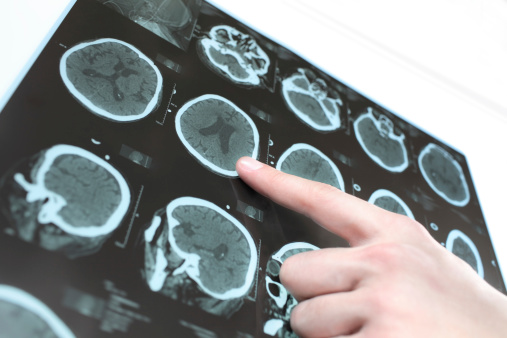

Alzheimer’s & Brain Awareness Month: Alzheimer’s disease and sleep disorders, hallucinations, Alzheimer’s prevention

June marks the beginning of sunshine-filled days and outdoor activities, but it also happens to be Alzheimer’s and brain awareness month. This is a time where the health community bands together to raise awareness about Alzheimer’s disease and other forms of dementia. At Bel Marra, we want to do our part, so we have provided ...click here to read more